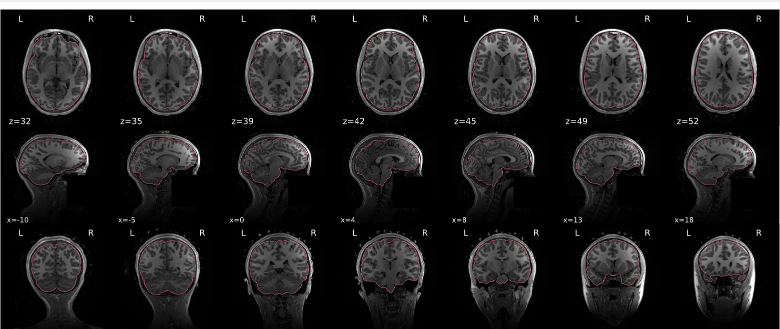

T1w skull stripping

Skull stripping is the process separating the brain (cortex and cerebellum) from the skull. The red line follows the outline of the brain and it separates it from the skull.

Example of a good subject

- There are no skull stripping errors, such as portions of the brain missing, or too much of the skull retained

- The red line follows the outline of the brain

Example of a bad subject

- There are skull stripping errors, such as portions of the brain missing, or too much of the skull retained

- NOTE: check all the images (slices) in the report. If only one image (slice) looks problematic, it is possible that the subject is okay and it is just a visual issue in that particular screenshot

Summary

| Good | Bad |

|---|---|

| The brain is fully inside the red line | Structures like the cranium or the eyes are inside the red line |

| No important brain structures are outside of the red line red line follows the natural outline of the brain | Important brain structures are missing inside of the red line |

-> if only one slice is problematic, it could be an issue related to the visual depiction of the data instead of an issue related to the test subject